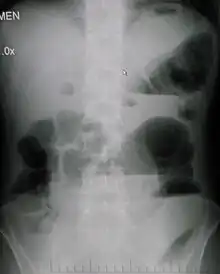

| Upright abdominal X-ray demonstrating a small bowel obstruction. Note multiple air fluid levels. | |

Causes of bowel obstruction include adhesions, hernias, volvulus, endometriosis, inflammatory bowel disease, appendicitis, tumors, diverticulitis, ischemic bowel, tuberculosis and intussusception.[1][2] Small bowel obstructions are most often due to adhesions and hernias while large bowel obstructions are most often due to tumors and volvulus.[1][2] The diagnosis may be made on plain X-rays; however, CT scan is more accurate.[1] Ultrasound or MRI may help in the diagnosis of children or pregnant women.[1]

Radiological signs of bowel obstruction include bowel distension and the presence of multiple (more than six) gas-fluid levels on supine and erect abdominal radiographs. Ultrasounds may be as useful as CT scanning to make the diagnosis.[13]